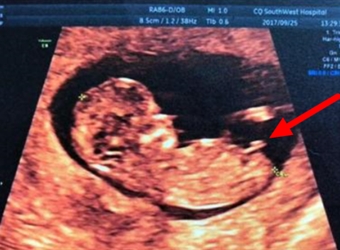

nt检查其实是B超检查的一种,主要是筛查畸形和唐氏综合征的胎儿,一般来说检查时间在孕12周左右,那么检查nt的时候可以看出来男女吗,看哪个数据能看出来男女…

网上流传的通过nt检查图的特征点判断男女宝宝的方式相信大家都有看过,那么nt图女宝的nub点为什么是平行的,做nt抱宝宝趴着是女宝吗?更多关于生男生女的相关…